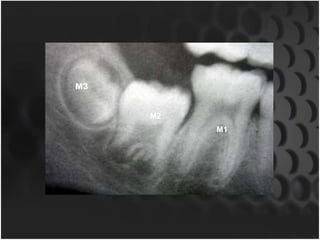

M3

M2

M1

Value Of ThirdMolar • Valuable indicator of age in 16-23yr old age gp.,where all other teeth have completely developed. • Its accuracy in age estimation is questionable due to great variation in its genesis,position,morphology & time of formation. • Gunst & associates underscore its importance due to inaccuracy of skeletal predictors of age in this age gp. • Age of an individual,specifically whether the individual is 18yrs old or not can reliably be estimated. • When all four 3rd molars have completely calcified,the individual being 18yr old is 96% & 95% for males & females respectively. • When all M3’s are not present(only 1 or 2 available for age estimation), » lower M3’s are better predictors of whether an individual is 18yrs old.